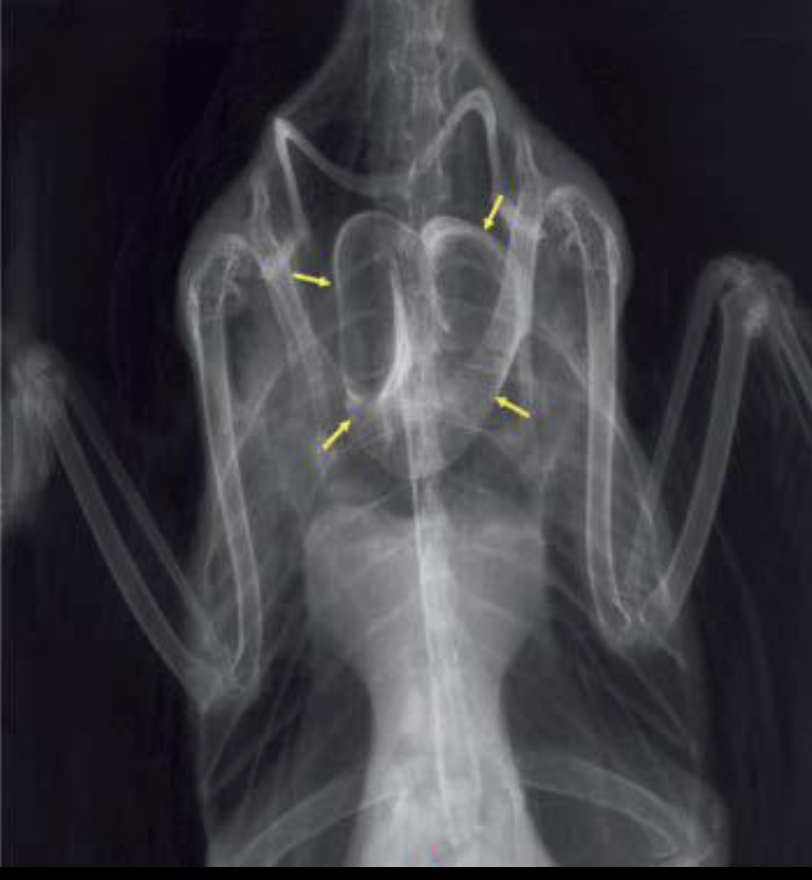

What are the parts of skeletal anatomy labelled in this image?

A

1: sternum

2: coracoid

3: clavicles/furcula

4: scapula